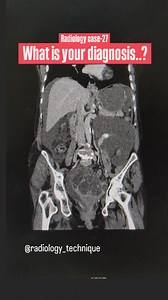

276 reactions · 15 shares | Radiology case -27 What is your diagnosis..? | Diwakar Patel | Facebook

Facebook

Diwakar Patel

已浏览 5万 次

2 周前